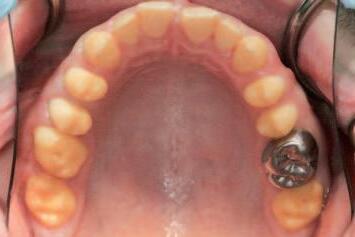

A 62-year-old man presented with a painful, firm, immobile swelling on the le border of the body of his mandible (Figure 1). Intra-orally no obvious dental pathosis was clinically visible, and his remaining le side mandibular teeth were unrestored, caries free, had no periodontal pocketing, were not tender to percussion, and were testing vital to cold testing. An orthopantomogram (OPG) was taken to assess further (Figure 2).

FIGURE 1

FIGURE 2

Quiz answers

1. Gardner syndrome.

2. Individuals who have Gardner syndrome may have hundreds or thousands of polyps in their small and large intestines, which puts them at a high risk of developing colon cancer. Oral features may include unerupted or impacted teeth, osteomas and supernumerary teeth.

3. Gardner syndrome is a rare inherited condition. It is caused by a mutation in the adenomatous polyposis coli (APC) gene. This gene is important in regulating cell growth. When the gene is faulty, cells can grow out of control,

clumping together to form abnormal growths. It is inherited in an autosomal dominant pattern.

4. Gardner syndrome may be suspected in individuals who have more than 100 polyps during colonoscopy procedures. Dentists may also notice features such as impacted teeth, osteomas and supernumerary teeth from radiographs. Genetic testing is needed for definitive diagnosis.

Questions on page 7